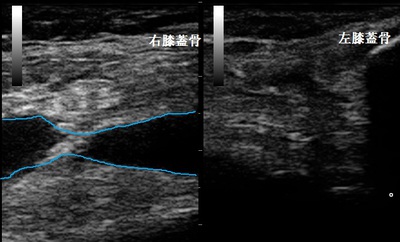

右膝上超音波長軸像 左同部 健側

来院時に超音波検査を実施したところ、右膝の滑液包に関節液(水腫)が過剰に溜まっている様子が認め

られました(画像の青い線)。